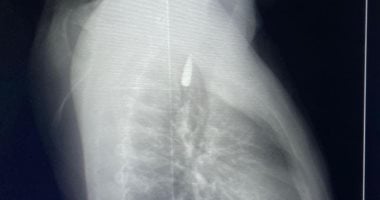

إنجاز طبى جديد بجامعة الإسكندرية لإنقاذ مريض فلسطينى مصاب من قطاع غزة

وأعرب الدكتور عبد العزيز قنصوة، رئيس جامعة الإسكندرية، عن فخره بهذا النجاح الذي يجسد الكفاءة العالية للفريق الطبي بالمستشفيات الجامعية، مؤكدًا أن الجامعة تولي اهتمامًا بالغًا بدعم القضايا الإنسانية وبتقديم الرعاية الصحية المتكاملة للأشقاء العرب، تنفيذًا لتوجيهات الدولة المصرية في مساندة المصابين من...